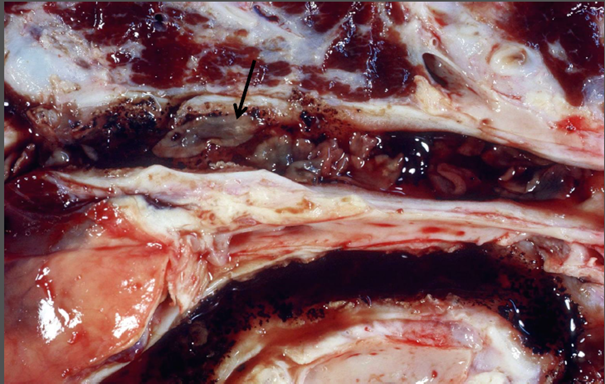

Leber

Beschreibung:

• Viszeral: Gallengänge stellen sich als weiße und derbe

Stränge dar

• hochgradig verdickte Wände von Gallengängen / die Wände

dieser Gallengänge sind hochgradig verdickt und

teilweise mineralisiert

• Adulte blatt-/lanzettförmige Trematoden (Pfeil) und

Gallekonkremente im Lumen

Diagnose:

• (Grad), Multifokale, chronischfibrosierende

Cholangitis und Pericholangitis mit

Gallengangsobstruktion

Fasziolose

Ätiologie:

• Rind und Schaf: Fasciola hepatica („großer Leberegel“)

Pathogenese:

• Chronische pericholangiäre und cholangiäre Fibrose durch in den größeren Gallengängen lebende Adulte

• Gallengangsobstruktion führt zur Stenose und Ektasie sowie periduktulärer Fibrose, im weiteren Verlauf zu Cholestase (Porphyrin-Eisen-

Pigmente)

Zusatzinfo:

• Entwicklung über Zwischenwirt (Lymnaea) → Tiere nehmen Metazerkarien aus Umwelt auf, Wanderung über Darm in Leber, dort ‘‘akute

Fasziolose‘‘ (Wanderwege zu den Gallengängen)

• Ausscheidung der Eier über die Galle